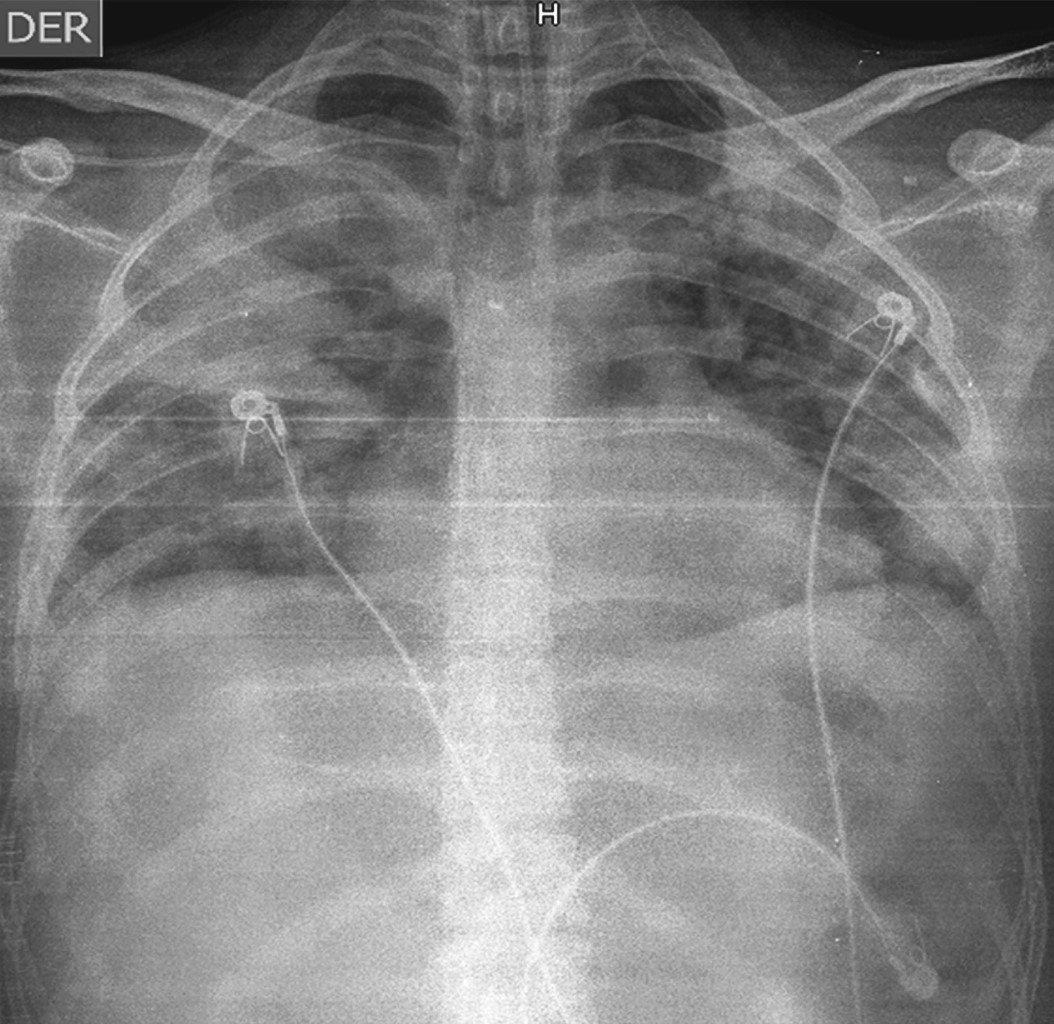

Paciente de 19 años de edad quien sufre accidente de tránsito en calidad de conductor de motocicleta por colisión contra una tractomula, lo que le ocasiona fractura diafisaria de fémur tibia y peroné en extremidad inferior derecha; se descarta etilismo en el sitio del accidente. Es llevado a centro de referencia donde presenta deterioro de la oxigenación por lo que requiere atención en Unidad de Cuidados Intensivos (UCI). Sin antecedentes de importancia familiares o personales, ingresa a UCI con índices de oxigenación alterados saturando 85% con mascara de no reinhalación, frecuencia respiratoria de 38 por minuto, frecuencia cardiaca de 100 por minuto, tensión arterial 90/55 mmHg, sin deterioro neurológico, Glasgow 15/15, temperatura de 38.5 oC. Al examen físico se documentan ruidos cardiacos taquicárdicos, ruidos respiratorios con crépitos bibasales y hematoma en región proximal del muslo con deformidad en tercio distal y exposición de material óseo. Se plantea la impresión diagnóstica de insuficiencia respiratoria aguda, embolismo graso y politraumatismo con múltiples fracturas en extremidad inferior derecha. Se realiza inducción de secuencia rápida con sedación analgesia y relajación, laringoscopía directa, Cormack-Lehane IV; se avanza tubo orotraqueal 7 con guía, previa BURP, sin registrar eventualidades.4,5 Mecánica ventilatoria seriamente afectada con distensibilidad estática de 18 cm, dinámica de 13 cm, presión meseta de 25 cm con presión de conducción de 18 cm y lesión pulmonar severa con PaO2/FiO2 de 85, por lo que se inicia protección pulmonar y titulación de presión positiva al final de espiración (PEEP) por bucle cuasiestático de presión y de volumen a partir de puntos de inflexión direccionado por EXPRESS.6,7 Se avanza línea central subclavia derecha, documentándose perfil distributivo, con predictores de bajo gasto por elevación del gradiente venoarterial de dióxido de carbono en 14 mmHg y predictores de hipoperfusión tisular por elevación del cociente metabólico anaeróbico de 2; adicionalmente acidemia metabólica profusa, consumo de base exceso severo e hiperlactatemia de 4,8,9 sin modificación de la masa globular. Ante evolución clínica, se inician terapias tempranas dirigidas por objetivos.10 Una radiografía de tórax de ingreso documenta infiltrados en los cuatro campos pulmonares con imagen sugestiva de joroba de Hampton sobre la cisura mayor (Figura 1); se presume enfermedad pulmonar tromboembólica y síndrome de dificultad respiratoria del adulto de origen pulmonar por criterios de redefinición de Berlín ante distensibilidades menores a 40 cmH2O; requerimiento de PEEP de 15 cmH2O, hallazgos radiológicos y volumen corregido espirado mayor a 10, por lo que continua protección pulmonar.11,12 Los estudios de laboratorio de ingreso se presentan resumidos en la Tabla 1. Se realiza ecocardiograma Doppler dúplex color transtorácico con el que se documenta hipertensión pulmonar moderada con 50 mmHg, fracción de eyección de 60% sin trastornos de la contractilidad. Marcadores de actividad fibrinolítica > 3,000 mg/dL, que confirman síndrome de dificultad respiratorio del adulto severo de origen pulmonar; reporte de sudan en orina descarta embolia grasa. Es llevado a cirugía para reducción y estabilización de la fractura sin eventualidad. Ante los hallazgos radiológicos, se realiza estudio de perfusión en medicina nuclear con el que se evidencian cuatro defectos segmentarios de distribución vascular en el pulmón derecho y tres en el pulmón izquierdo (Figura 2). Por lo que continua anticoagulación formal. Ante tórpida evolución con lesión pulmonar severa, PaO2/FiO2 de 65, deterioro de la ventilación minuto alveolar con capnografías que indican hipoventilación alveolar con registros hasta de 75 mmHg de dióxido de carbono al final de la espiración y mayor compromiso de la impedancia pulmonar con presión de conducción de 19 cmH2O y cálculo de poder mecánico en 15 julios, se decide iniciar estrategia de rescate con insuflación de gas traqueal a partir de fuente adicional de oxígeno con dispositivo médico CONCOA 305260 más protección pulmonar extrema ante el riesgo elevado de lesión pulmonar inducida por el respirador.13-16 La Tabla 2 muestra los datos de la evolución gasométrica. Se reciben reportes de cultivos de vigilancia; se documentan enterobacterias con resistencias extendidas inductoras de anhidromuropéptidos en hisopado y pandrogorresistencias en lavado broncoalveolar, lo cual genera la necesidad de descartar alguna inmunodeficiencia por lo que se realiza serología para virus de la inmunodeficiencia humana (VIH) la cual fue negativa.17 Se realizan estudios de hipercoagulabilidad ante la complejidad clínica, cuyos resultados se muestran en la Tabla 3. Presenta alteración mental, pensamiento desorganizado, inatención y conciencia fluctuante con PRE-DELIRIC > 40, por lo que requiere protocolo institucional de sedación, dolor y delirio.18 Evoluciona favorablemente con adecuada respuesta a terapias tempranas dirigidas por objetivos. Adicionalmente, se observa mejoría de la oxigenación y de la ventilación, así como de la mecánica ventilatoria, además de cálculo de índice de oxigenación menor a 10, por lo que se inicia ventilación mecánica protectora y se suspende insuflación de gas traqueal. Se realiza monitoria en asa cerrada en modo ventilación con asistencia proporcional; se documenta distensibilidad de 58 cmH2O, resistencias de 4.8 cmH2O, PEEP intrínseco de 1.2 cmH2O, elastasia de 16 cmH2O, relación frecuencia volumen de 25 con trabajo respiratorio de 0.8 J/L.19 Se realiza prueba única diaria con tubo en T sin predictores de falla de extubación, se libera de manera direccionada con cánula de alto flujo para generación de inertancia por presión y temperatura.20,21 Evoluciona favorablemente, por lo que se traslada a pisos para continuar manejo por medicina interna.

Figura 1